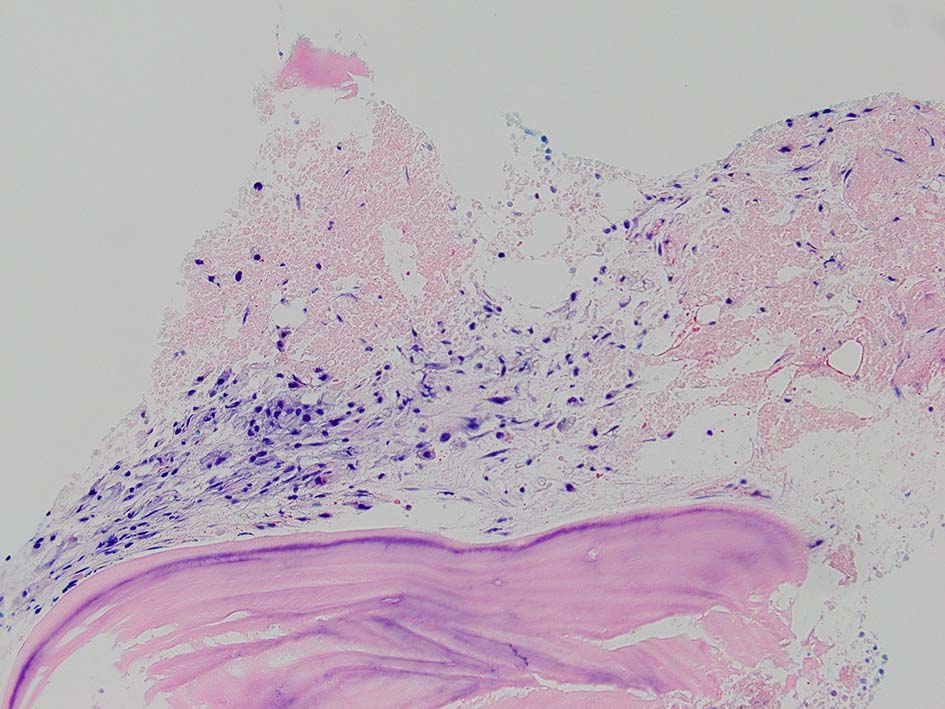

骨髄壊死(BMN)は,造血性骨髄(BM)の髄質間質と骨髄組織の広範囲な壊死を特徴とするユニークな臨床病理学的病態であり、無定形の好酸球性背景、由来不明瞭な壊死細胞、皮質骨の温存が認められる.*1

骨髄生検組織では骨梁間に壊死に陥った細胞の凝固壊死像が確認できる. 本例では脂肪細胞は消失せず形態が残っている.壊死のあとには, 髄腔に線維化をきたす. 上図には線維化を示し, 右端の図では壊死巣と線維化の境界が観察される.

本例ではviableな腫瘍細胞がハーバース管内(?)に認められた.(髄腔とハーバース管腔は解剖学的に同じ場所といえるのか?)